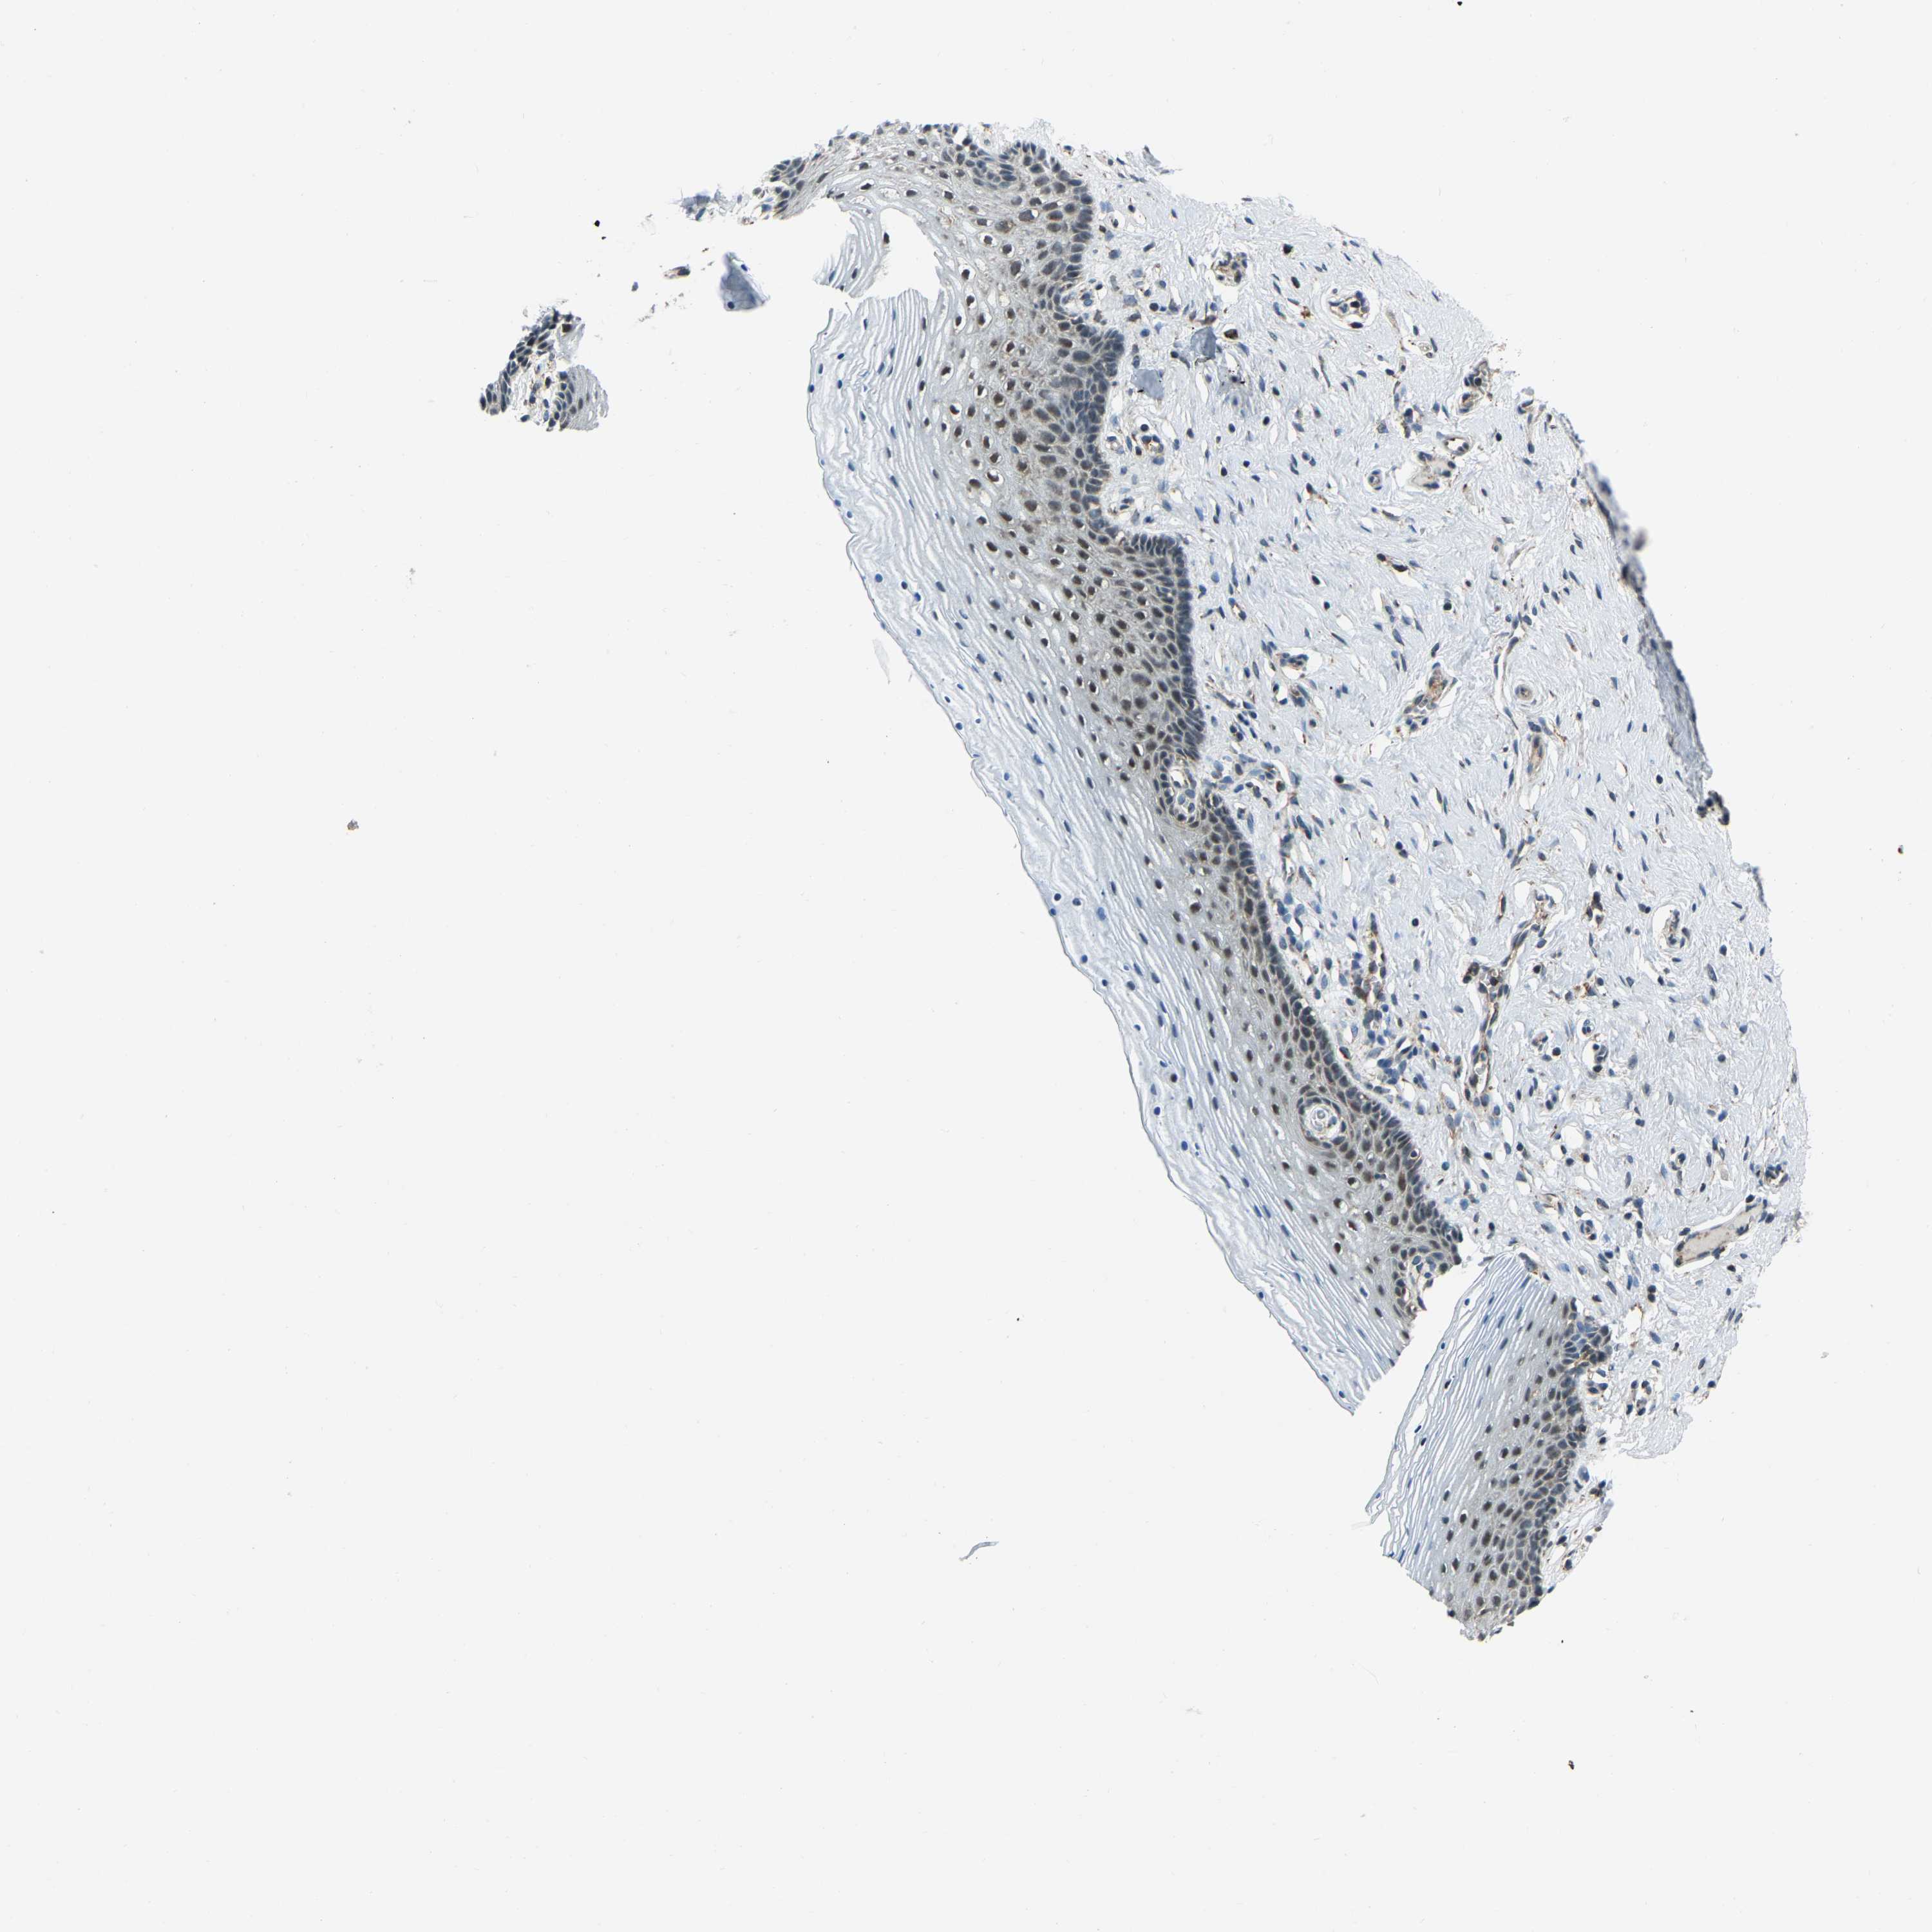

VAGINA - Antibody stainingi

Antibody staining in the annotated cell types in the current human tissue is reported as not detected, low, medium, or high, based on conventional immunohistochemistry profiling in selected tissues. This score is based on the combination of the staining intensity and fraction of stained cells.

Each image is clickable and will lead to virtual microscopy that enables deeper exploration of all samples and also displays staining intensity scores, fraction scores and subcellular localization as well as patient and tissue information for each sample.

Antibody HPA019232Antibody HPA021497Antibody HPA021768

Squamous epithelial cells LowNot detectedHigh